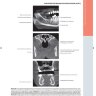

Примеры страниц из книги "Лучевая диагностика. Полость рта и челюстно-лицевая область" - Кениг, Лиза Дж., Тамими Дания, Петриковски С. Грейс